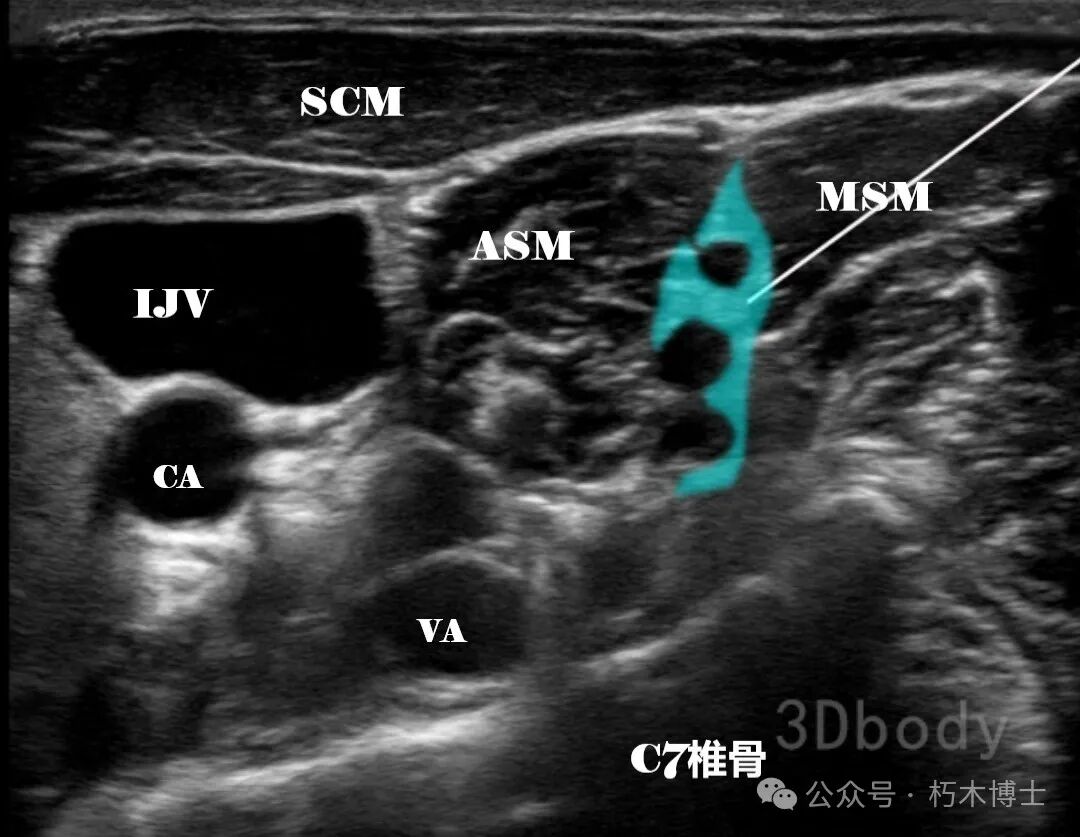

**臂丛神经阻滞的不同入路****一、肌间沟入路**1. 解剖:C5~C8 及 T1 神经的前支穿出椎间孔后,在前、中斜角肌间隙内合并形成上干(C5 与 C6)、中干(C7)和下干(C8 与 T1);穿出肌间沟后于锁骨下动脉的后上方沿第一肋骨上缘穿行。2. 适用手术:主要用于肩部和上臂近端的手术,用于前臂和手部手术时需追加尺神经阻滞。3. 超声解剖图:肌间沟水平的臂丛位于颈动脉外侧,前、中斜角肌之间。浅层可见椎前筋膜、颈浅丛和胸锁乳突肌,1~3cm 深度处可见臂丛。

![]()

图1. SCM:胸锁乳突肌;ASM:前斜角肌;MSM:中斜角肌;IJV:颈内静脉;CA:颈动脉;VA椎动脉。黑色串珠状结构为臂丛,浅蓝色为注射区域,白色直线为注射针。(图源:3Dbody)

4. 操作要点: - 患者取仰卧位或半坐卧位,头转向对侧。 - 高频探头横向放置在颈部,颈动脉搏动处,约在锁骨上 3~4cm。 - 看到颈动脉后向外侧滑动探头,直至出现前、中斜角肌及肌间沟中的臂丛结构。 - 确定目标后,平面内技术由外向内进针,穿过椎前筋膜。 - 回抽无血、脑脊液后,注入 15~20ml 局麻药,确保包绕相关神经干。**二、锁骨上入路**1. 解剖:阻滞位于臂丛神经干的远端与神经股的近端之间的水平。2. 适用手术:适合肘、前臂及手掌部位手术。3. 超声解剖图:锁骨下动脉在锁骨中点,前、中斜角肌之间穿过第一肋。锁骨下动脉深部、侧面的线状高回声结构是胸膜和第一肋,深部低回声的是肺。臂丛呈椭圆形或扁平形。